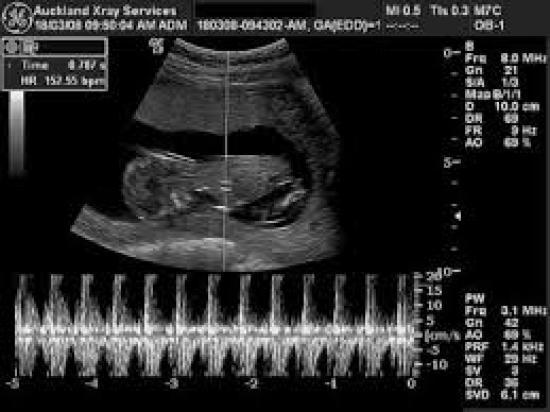

43+ Free Pregnancy Ultrasound Auckland Pictures. It is a tool that can provide information and answer questions you may have about what is happening inside your body. Horizon radiology is a new zealand owned business that offers a wide range of diagnostic imaging services including; These waves create echoes, which are recorded and displayed in real time on a monitor. It is painless and used in most soft tissue areas of the body. Your doctor, midwife or physio will refer you to have an ultrasound.

Pregnancy ultrasound in central auckland search for pregnancy ultrasound services within central auckland we have 9 services in central auckland matching your criteria. Horizon radiology is a new zealand owned business that offers a wide range of diagnostic imaging services including; 09/06/2021 · pregnancy ultrasound in central auckland search for pregnancy ultrasound services within central auckland we have 10 services in central auckland matching your criteria. The main types of scans are: Your doctor, midwife or physio will refer you to have an ultrasound. Early pregnancy dating scans remain free of charge for all. It is a tool that can provide information and answer questions you may have about what is happening inside your body. It is painless and used in most soft tissue areas of the body. Between 6 and 11 weeks gestation: Where the probe is moved over your skin. Scans typically last between 30 and 45 minutes. These waves create echoes, which are recorded and displayed in real time on a monitor. Ultrasound is a type of diagnostic medical imaging system which uses sound waves above the threshold of hearing to capture live images from within your body.